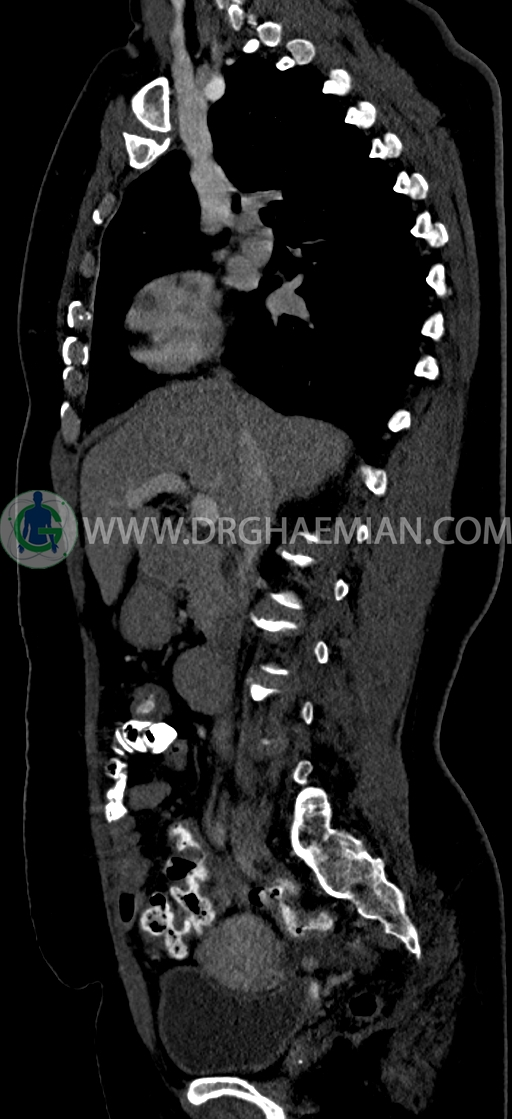

در سي تي اسکن اسپيرال ريه و مدياستن-شکم و لگن با کنتراست خوراکی و وريدی (مولتي ديدکتور 16 با مقاطع ظريف و بازسازي هاي ساژيتال و کرونال) :

-فيبروم اينترامورال- ساب سروزال به سايز 35mm در قدام فوندوس با اثر فشاري بر ديواره فوقاني مثانه

-هرني سوپرا امبليکال با ديفکت به سايز 10mm حاوي چربي و هرني امبليکال با ديفکت به سايز 7mm حاوي چربي مشهود است.

-فوليکول به سايز 21mm همراه با مايع آزاد جزئي در لگن مطرح کننده اوولاسيون